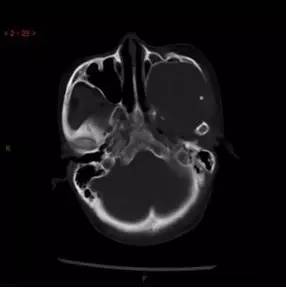

CT骨窗轴位

解析:本病例为中颅窝至颞下窝沟通性病变,对周围骨质主要呈膨胀压迫性改变,伴囊变、出血。